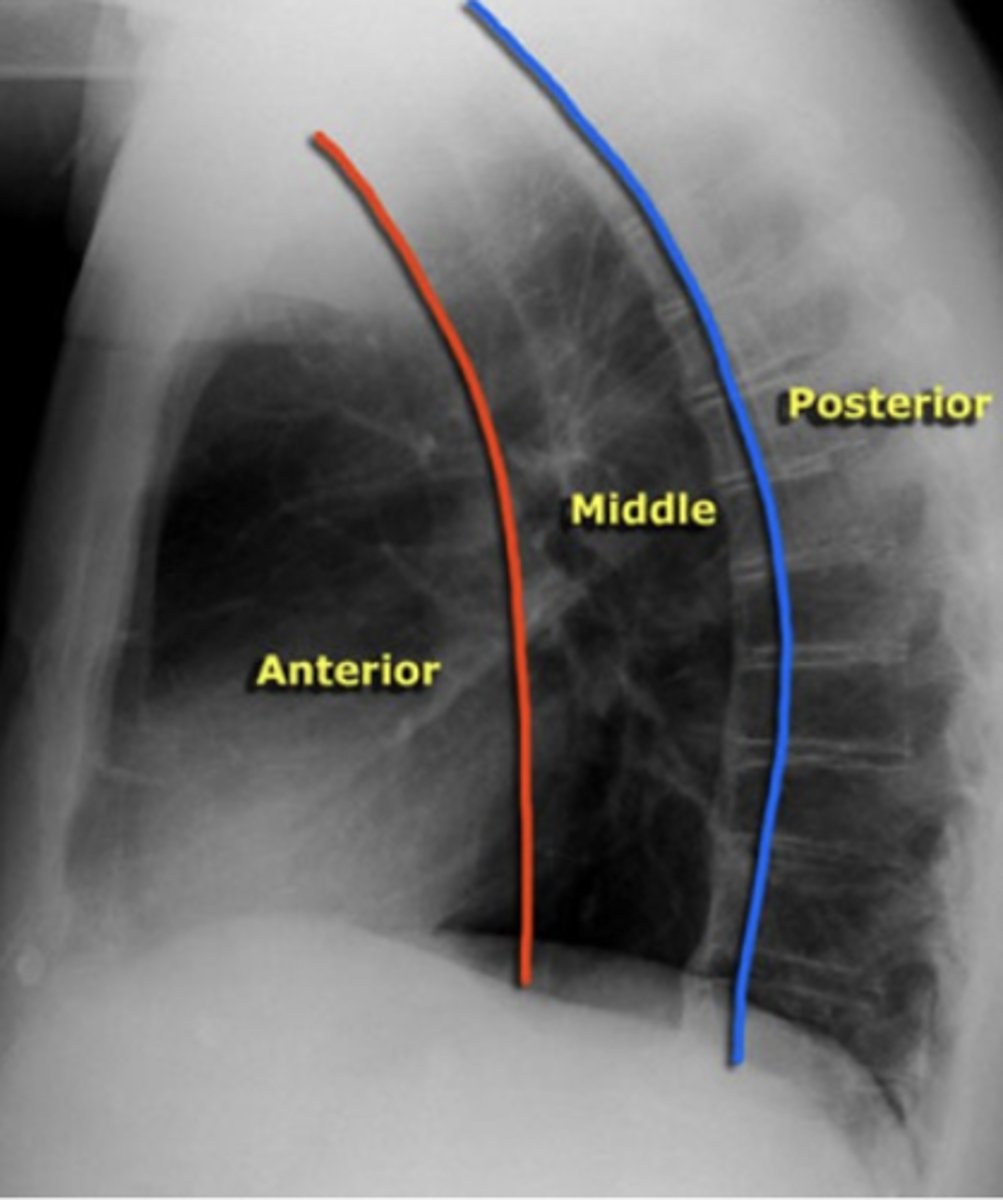

ascending aorta, aortic knob, heart, lymph nodes, thyroid, and thymus

What structures are located in the anterior mediastinal compartment?

esophagus, trachea, lymph nodes, and aortic arch

What structures are located in the middle mediastinal compartment?

descending aorta, lymph nodes, spinal nerves, and vertebral bodies.

What structures are located in the posterior mediastinal compartment?